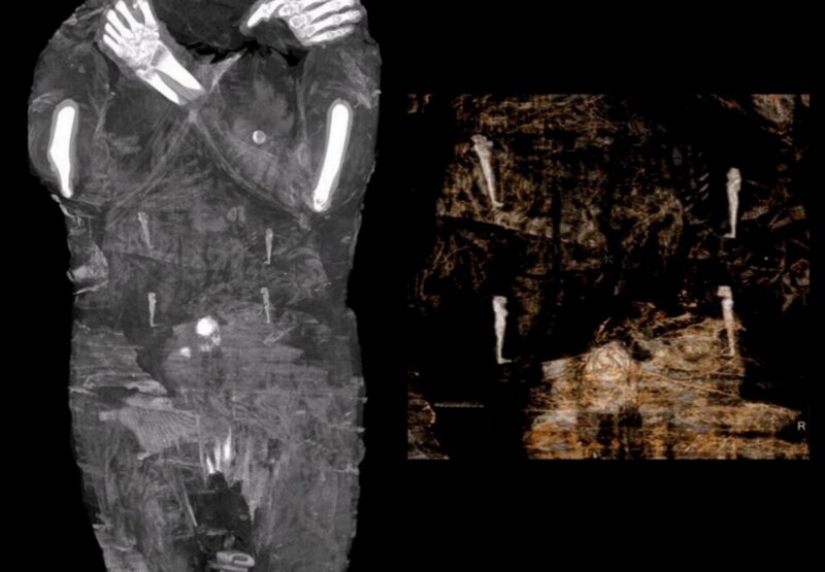

Por Pictolic https://mail.pictolic.com/es/article/hallazgo-nico-momia-egipcia-result-estar-embarazada.htmlLa Academia Polaca de Ciencias escaneó todas las momias del antiguo Egipto en los museos locales e hizo un descubrimiento interesante. Una de las momias, que anteriormente se pensaba que era un hombre, resultó ser una mujer de 20 años que fue embalsamada con un feto dentro.

Un grupo de científicos polacos descubrió que una momia egipcia, que anteriormente se pensaba que era un hombre, es en realidad una mujer en las últimas etapas del embarazo. Parece ser el único ejemplo conocido de una momia egipcia embarazada embalsamada.

La momia, que se encuentra en el Museo Nacional de Varsovia (Polonia) desde 1917, fue encontrada en las Tumbas Reales de Tebas en la década de 1800. Fue embalsamada hace unos 2 mil años, cuando reinó Cleopatra.

La momia embarazada fue llevada a Varsovia en 1826. La inscripción en su ataúd indicaba que se trataba de una figura religiosa masculina, un sacerdote llamado Khor-Dehuti. Hasta hace poco, ningún examen preliminar de la momia indicaba que pudiera ser una mujer.

Para el nuevo estudio, los científicos decidieron escanear el cuerpo y se sorprendieron al encontrar que, de hecho, una mujer en el séptimo mes de embarazo está acostada en el ataúd.